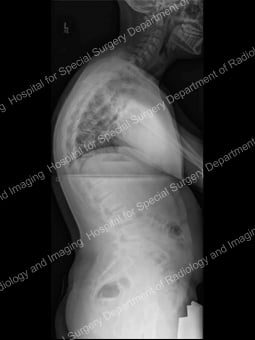

Adolescent idiopathic scoliosis a condition in which the spine is curved sideways in one or more areas [Figure 1], with no known cause. This different from that in the condition known as kyphosis, where the spine has an abnormal, forward-oriented curvature [Figure 2]. It affects girls more frequently than boys.

Figure 2: Lateral (side) view of the spine (standing) demonstrates kyphosis in the thoracic spine. |

To assess the curve further, X-ray images or low-dose radiation EOS images are taken from the front and side views [Figures 4, 5]. Side-bending X-rays may also be taken to assess the flexibility of the curve or curves. Sometimes these images reveal two curves: the first curve to appear in the spine (the primary curve) and the compensatory curve that the patient develops through his or her effort to maintain an erect posture.

Figures 4 (left) & 5 (right): Anterior to posterior (front to back) and lateral

(side) X-rays showing a scoliosis curve from the back and side, respectively.